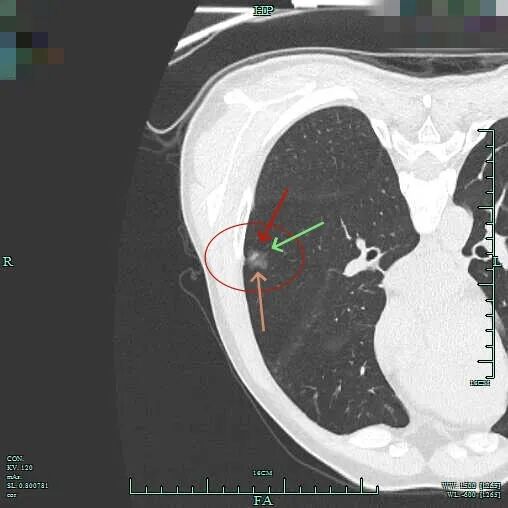

病灶处叶间裂密度较高,灶内有条状偏高密度,磨玻璃成分较淡。

灶内密度欠均匀,紧贴叶间裂,部分边缘略毛糙,整体轮廓清楚。